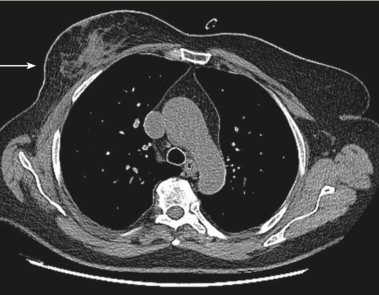

The role of preoperative axillary ultrasound and fine-needle aspiration cytology in identifying patients with extensive axillary lymph node involvement

MagyarPreoperative axillary nodal staging of invasive lobular breast cancer with ultrasound guided fine needle aspiration in patients with suspicious ultrasound findings versus aspiration in all patients e A retrospective single institutional analysis